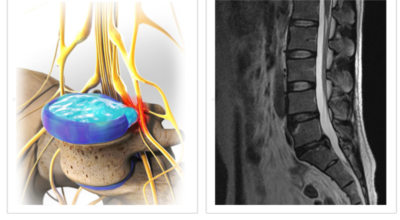

디스크(추간판)의 한가운데에는 젤리같이 찐득찐득한 '수핵'이라 하는 물질이 들어 있어요. 그 주변에 수핵을 둘러싸는 '섬유륜'이라 하는 두꺼운 막이 있는데 디스크는 전체적으로 자동차의 타이어와 같은 형태라고 합니다.

디스크는 일어선 상태에서는 중력을 받아 납작해져서 바깥쪽으로 약간 볼록한 형태가 된다고 합니다. 디스크는 그 특수한 구조 때문에 웬만한 힘이 가해져도 효율적으로 쿠션 역할을 할 수 있겠습니다. 그러나 급작스럽게 무거운 물건을 들어 올리거나, 부자연스러운 자세를 오랜 시간 취하면 디스크에 무리한 힘이 가해지면서 디스크가 밖으로 돌출이 되게 돼요. 심한 경우 디스크를 감싼 막이 터지면서 그 안에 있는 수핵이 튀어나오게 돼요.

디스크는 대개 후방이나 후외방으로 돌출되는데 이때 바로 곁에 있는 신경을 누르게 된다고 합니다. 돌출된 디스크는 척추의 어느 부위에나 일어날 수 있어요. 목에 생기면 '목 디스크', 등에 생기면 '등 디스크', 허리에 생기면 '허리 디스크'라고 부른다고 합니다.

이와 같이 디스크가 돌출되어 신경을 눌러 요통 또는 다리가 아프고 저린 증상을 유발하는 병을 '추간판 탈출증' 및 '디스크 탈출증'이라고도 불러요. 발생 빈도별로 보면 허리 디스크가 가장 흔합니다. 그다음이 목 디스크이지요. 등 디스크는 드문 병이라고 합니다.